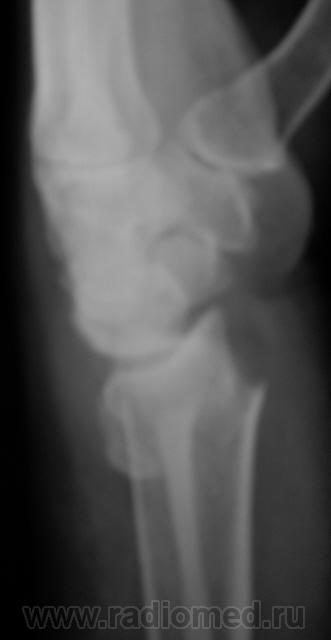

Случай 2.  Пациент направлен врачом хирургом на рентгенографию лучезапястного сустава.